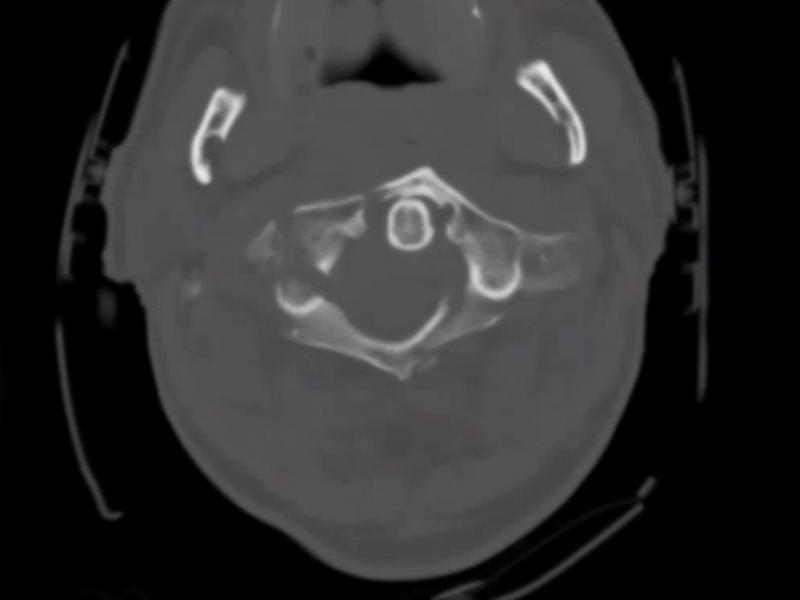

What's the diagnosis? By Dr. Lynn Manganiello

August 14 2019